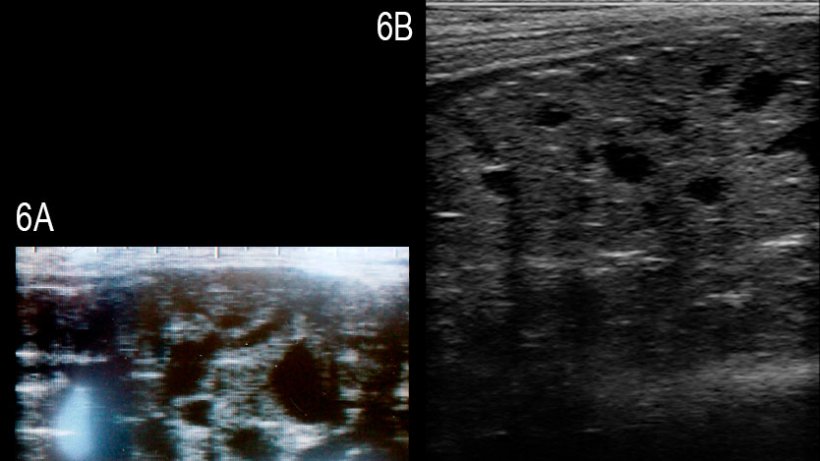

Les études sur l'utilisation pratique de l'échographie dans la reproduction des verrats sont rares. Le diamètre des testicules a été déterminé afin de le relier avec le nombre total de spermatozoïdes produits dans un éjaculat moyen (Clark et al., 2003) ou pour évaluer le développement pubertaire (Ford et Wise, 2010). La corrélation du diamètre des deux testicules et du nombre total de spermatozoïdes a été mauvaise, au moins chez les verrats de plus de 8 mois; la détermination de la taille testiculaire des plus jeunes verrats, d'environ 4 mois, a semblé utile pour la prédiction du volume des testicules et de la production de sperme lorsque le verrat avait atteint la maturité. Il y a un rapport récent sur un verrat Large White infertile avec une dégénérescence multikystique de la glande bulbo-utétrale; dans la glande affectée on visualise des kystes anéchogéniques solides et bien définis de différentes tailles (Figure 6, Grahofer et al., 2016)

Figure 6: Images de la glande bulbo-urétrale d'un verrat atteint par de multiples kystes anéchogéniques bien définis de différentes tailles (A) et d'un verrat sain (B) (Grahofer et al., 2016).